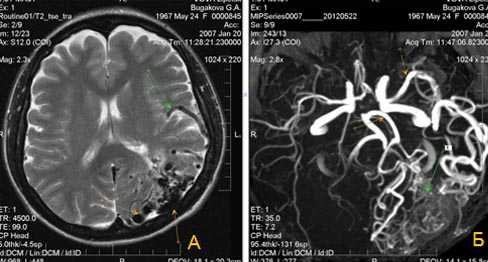

(а) МРТ (рутинное обследование), FLAIR, аксиальный срез: у мужчины 18 лет с семейным анамнезом, отягощенным наследственными геморрагическими телеангиоэктазиями (НГТ), в медиальном отделе лобной доли определяется зона гиперинтенсивного сигнала, связанная с участками потери сигнала за счет эффекта потока.

(б) МРТ, постконтрастное Т1-ВИ, аксиальный срез: у того же пациента отмечается интенсивное контрастное усиление выявленного участка. (а) МРТ, постконтрастное Т1-ВИ, корональный срез: у того же пациента определяется интенсивное контрастирование выявленного участка.

(б) ЦСА, латеральный снимок внутренней сонной артерии: у того же пациента определяется небольшая АВМ узловою типа с ранним дренированием вены. При генотипировании была обнаружена мутация пена ENG.